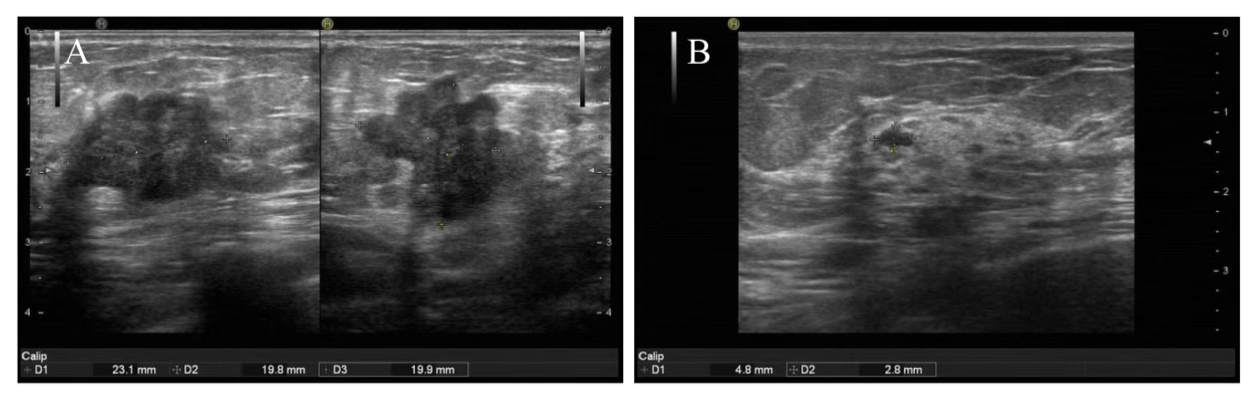

将miRNA-34a与上述筛选出的5个关键影像组学特征同时输入KNN分类器,构建新的联合模型,并通过ROC曲线对其进行评价。结果显示,联合模型在训练组和验证组中的AUC分别为0.875(95%CI 0.712~1.000)和0.875(95%CI 0.792~0.959),明显优于单一的临床模型和超声影像组学模型,见图1AB。DeLong检验结果显示,在验证组中,联合模型的性能优于单一临床模型(P = 0.015),高于超声影像组学模型,但差异无统计学意义(P = 0.057)。决策曲线分析进一步表明,联合模型在预测乳腺癌患者NAC后pCR方面表现出更高的临床实用性,见图1CD图2

图1 临床模型、超声影像组学模型、联合模型诊断表现

注:A、C为训练组,B、D为验证组。

Figure 1 Diagnostic performance of the clinical model, ultrasound radiomics model and joint model

图2 一例联合模型预测乳腺癌NAC患者pCR

注:A为NAC前乳腺癌病灶,B为NAC 3个周期后乳腺癌病灶;患者女,55岁,NAC前病灶大小约23.1 mm×19.8 mm×19.9 mm,联合模型预测达到pCR概率为0.857,在接受NAC 3个周期后,病灶大小4.8 mm×2.8 mm,达到pCR。

Figure 2 Joint model for predicting pathological complete response in one case of breast cancer patient after neoadjuvant chemotherapy